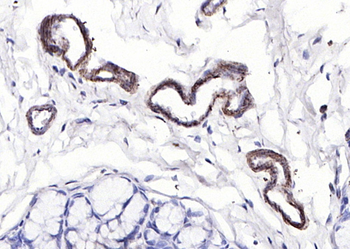

Phospho-Paxillin (Tyr88) Rabbit Polyclonal Antibody抗体

Phospho-Paxillin (Tyr88) Rabbit Polyclonal Antibody

IF, IHC-Fr, IHC-P, WB

KLH conjugated Synthesised phosphopeptide derived from human Paxillin around the phosphorylation site of Tyr88 PV(p-Y)GS

应用稀释比例:WB=1:500-2000, IHC-P=1:100-500, IHC-F=1:100-500, IF=1:100-500